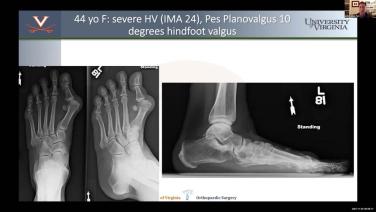

Master Class on Foot Deformities with Joseph Park, MD - Part 5